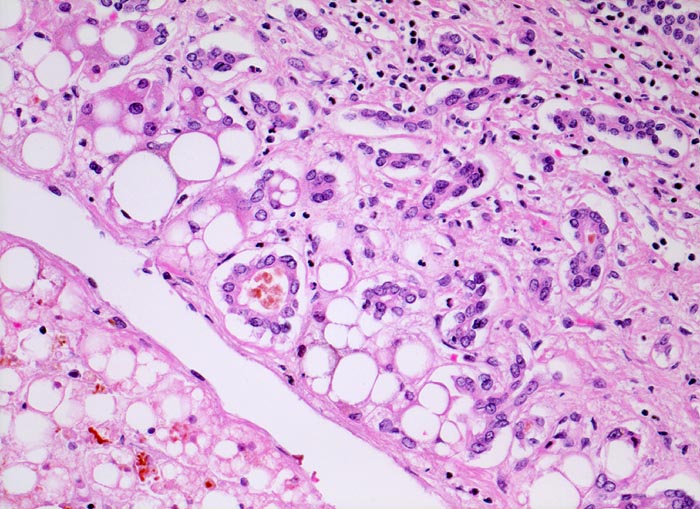

Steatose, Ductulusproliferation und septische Cholestase

Proliferierte Ductuli in der rechten Bildhälfte. Zwei Ductuli enthalten einen Gallepfropf. Ein Teil der grobtropfig verfetteten Hepatozyten enthält ebenfalls Galle.

Eine Cholestase bei Sepsis, Hämolyse oder Schock involviert typischerweise die Ductuli und die Hering Kanäle in der Peripherie der Portalfelder. Die betroffenen Ductuli sind dilatiert und enthalten einen Gallepfropf. Zusätzlich besteht oft eine Cholestase in der Läppchenperipherie.